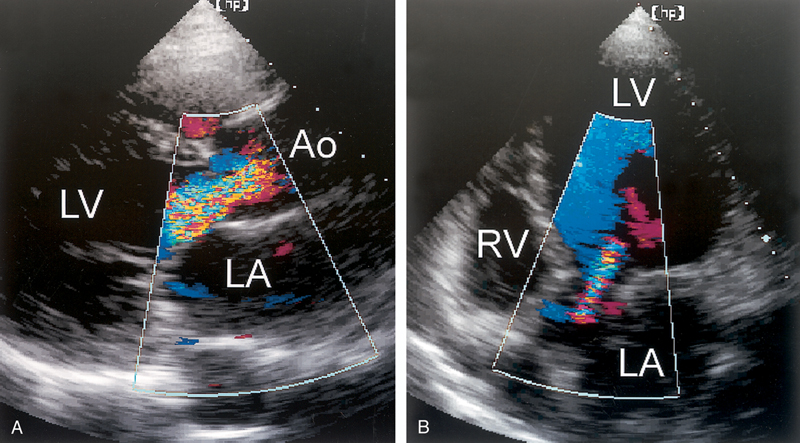

فحوصات تشخيصية لبعض امراض القلب والشرايين التاجية